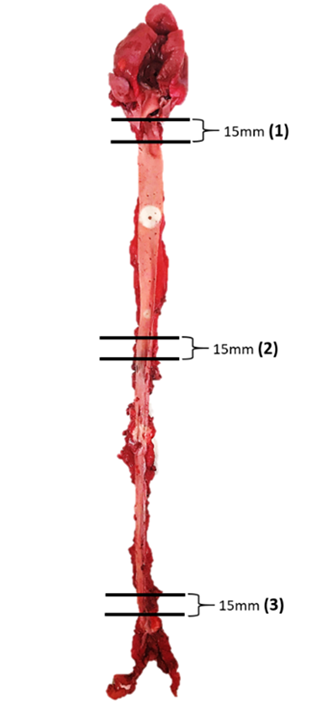

The histological examination of aorta in group A, the control group showed intact tunica intima with thin wavy corrugated endothelium, a normal subendothelial layer, and wavy internal elastic fibers. The tunica media is comprised of elastic fibers and smooth muscle. The outermost layer is the tunica adventitia and is made up of loose connective tissue (Figs. 7,8). In group B, the tunica intima showed the presence of focal thickening, filled with vacuolated cells or foam cells, resulting in the widening of the subendothelial layer (Fig. 9). The tunica intima of the aorta in group C showed intimal thickening with subendothelial collection of foam cells as well as formation of a lipid core and fibrous cap (Fig. 10).

Fig. 7.A photomicrograph of a section of the aorta in group A stained

by hematoxylin and eosin (10